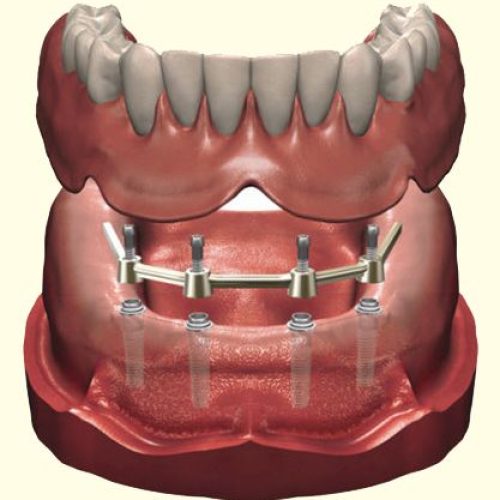

Dr Nitesh Rai, specializes in replacement of teeth with complete dentures, removable partial dentures, fixed partial dentures and Implants.

He has been actively involved in providing implant treatment for over two decades. He is also a committed academician, educating dental students and has been associated with Krishnadevaraya college of Dental sciences, Bengaluru as a Senior Professor, PG Guide and teacher in the Department of Prosthodontics, Crown and Bridge and Implant.